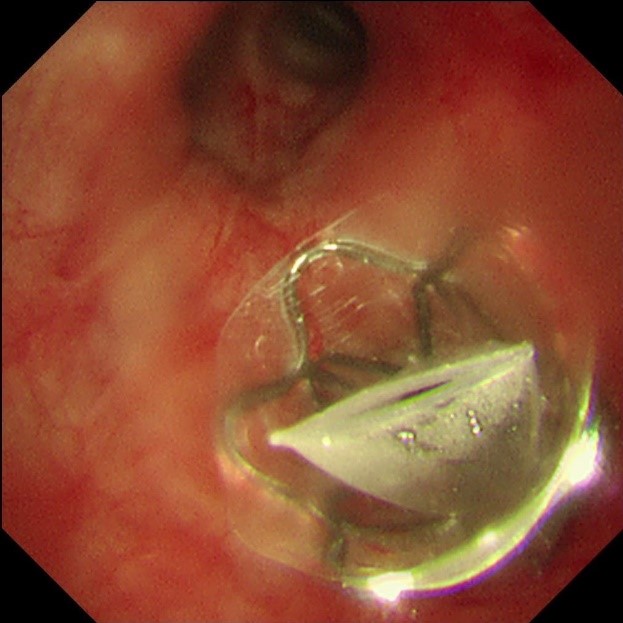

手术当天,蒋军红主任和曾大雄主任密切配合,用时30分钟便顺利完成手术。手术通过微创支气管镜介入,在高清内镜视野下,精准定位病变最严重的靶肺叶支气管,精准植入一枚微型支气管内活瓣(EBV-TS-5.5),术中实时验证活瓣开合状态良好,通气单向引流功能正常。

该技术的核心原理十分精妙:通过支气管镜将特制的微型单向活瓣,精准植入过度充气、丧失功能的病变肺叶支气管内,这个微型活瓣具备“只出不进”的独特功能——吸气时活瓣自动关闭,阻止外界气体进入病变废用肺叶;呼气时活瓣自动打开,让病变肺叶内残留的气体和分泌物顺利排出,从而促使靶肺组织逐渐萎陷、不张,达到肺减容的目的。